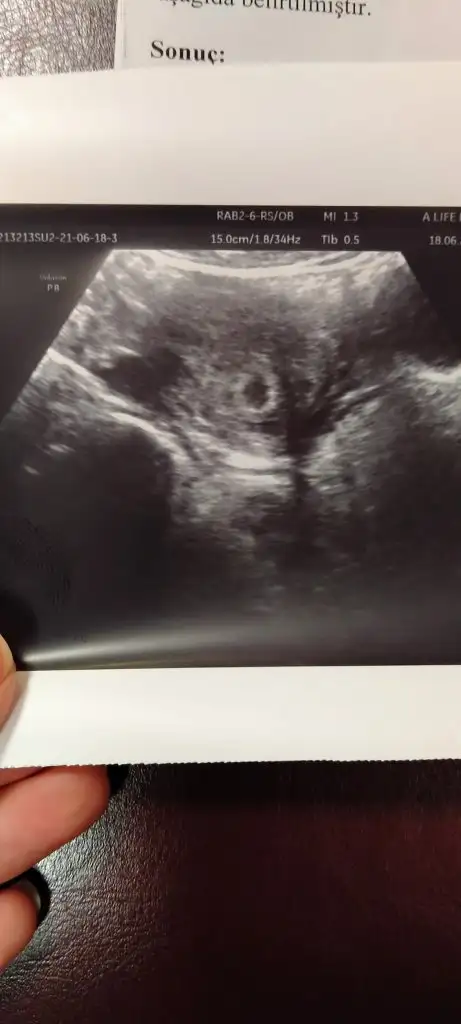

Merhaba bugün keseyi gördük 5+3 teyim. Ben folik asit, OMEGA 3 haricinde sadece Proluteks ve coraspin kullanıyorum. Bugün yeni bir doktora gittim ve proluteksi 3 ay olana kadar kullanacaksın dedi. Daha tüp bebek doktoruma sormadım ama size bir süre verildi mi?

Minnoşumun kalp atışını duydum ve gördüm çok şükür 😍gayet sağlıklı görünüyor kese de oldukça düzgün dedi doktor 😊 Rabbim isteyen herkese nasip etsin,hepimiz sağlıkla kavuşalım inşallah.